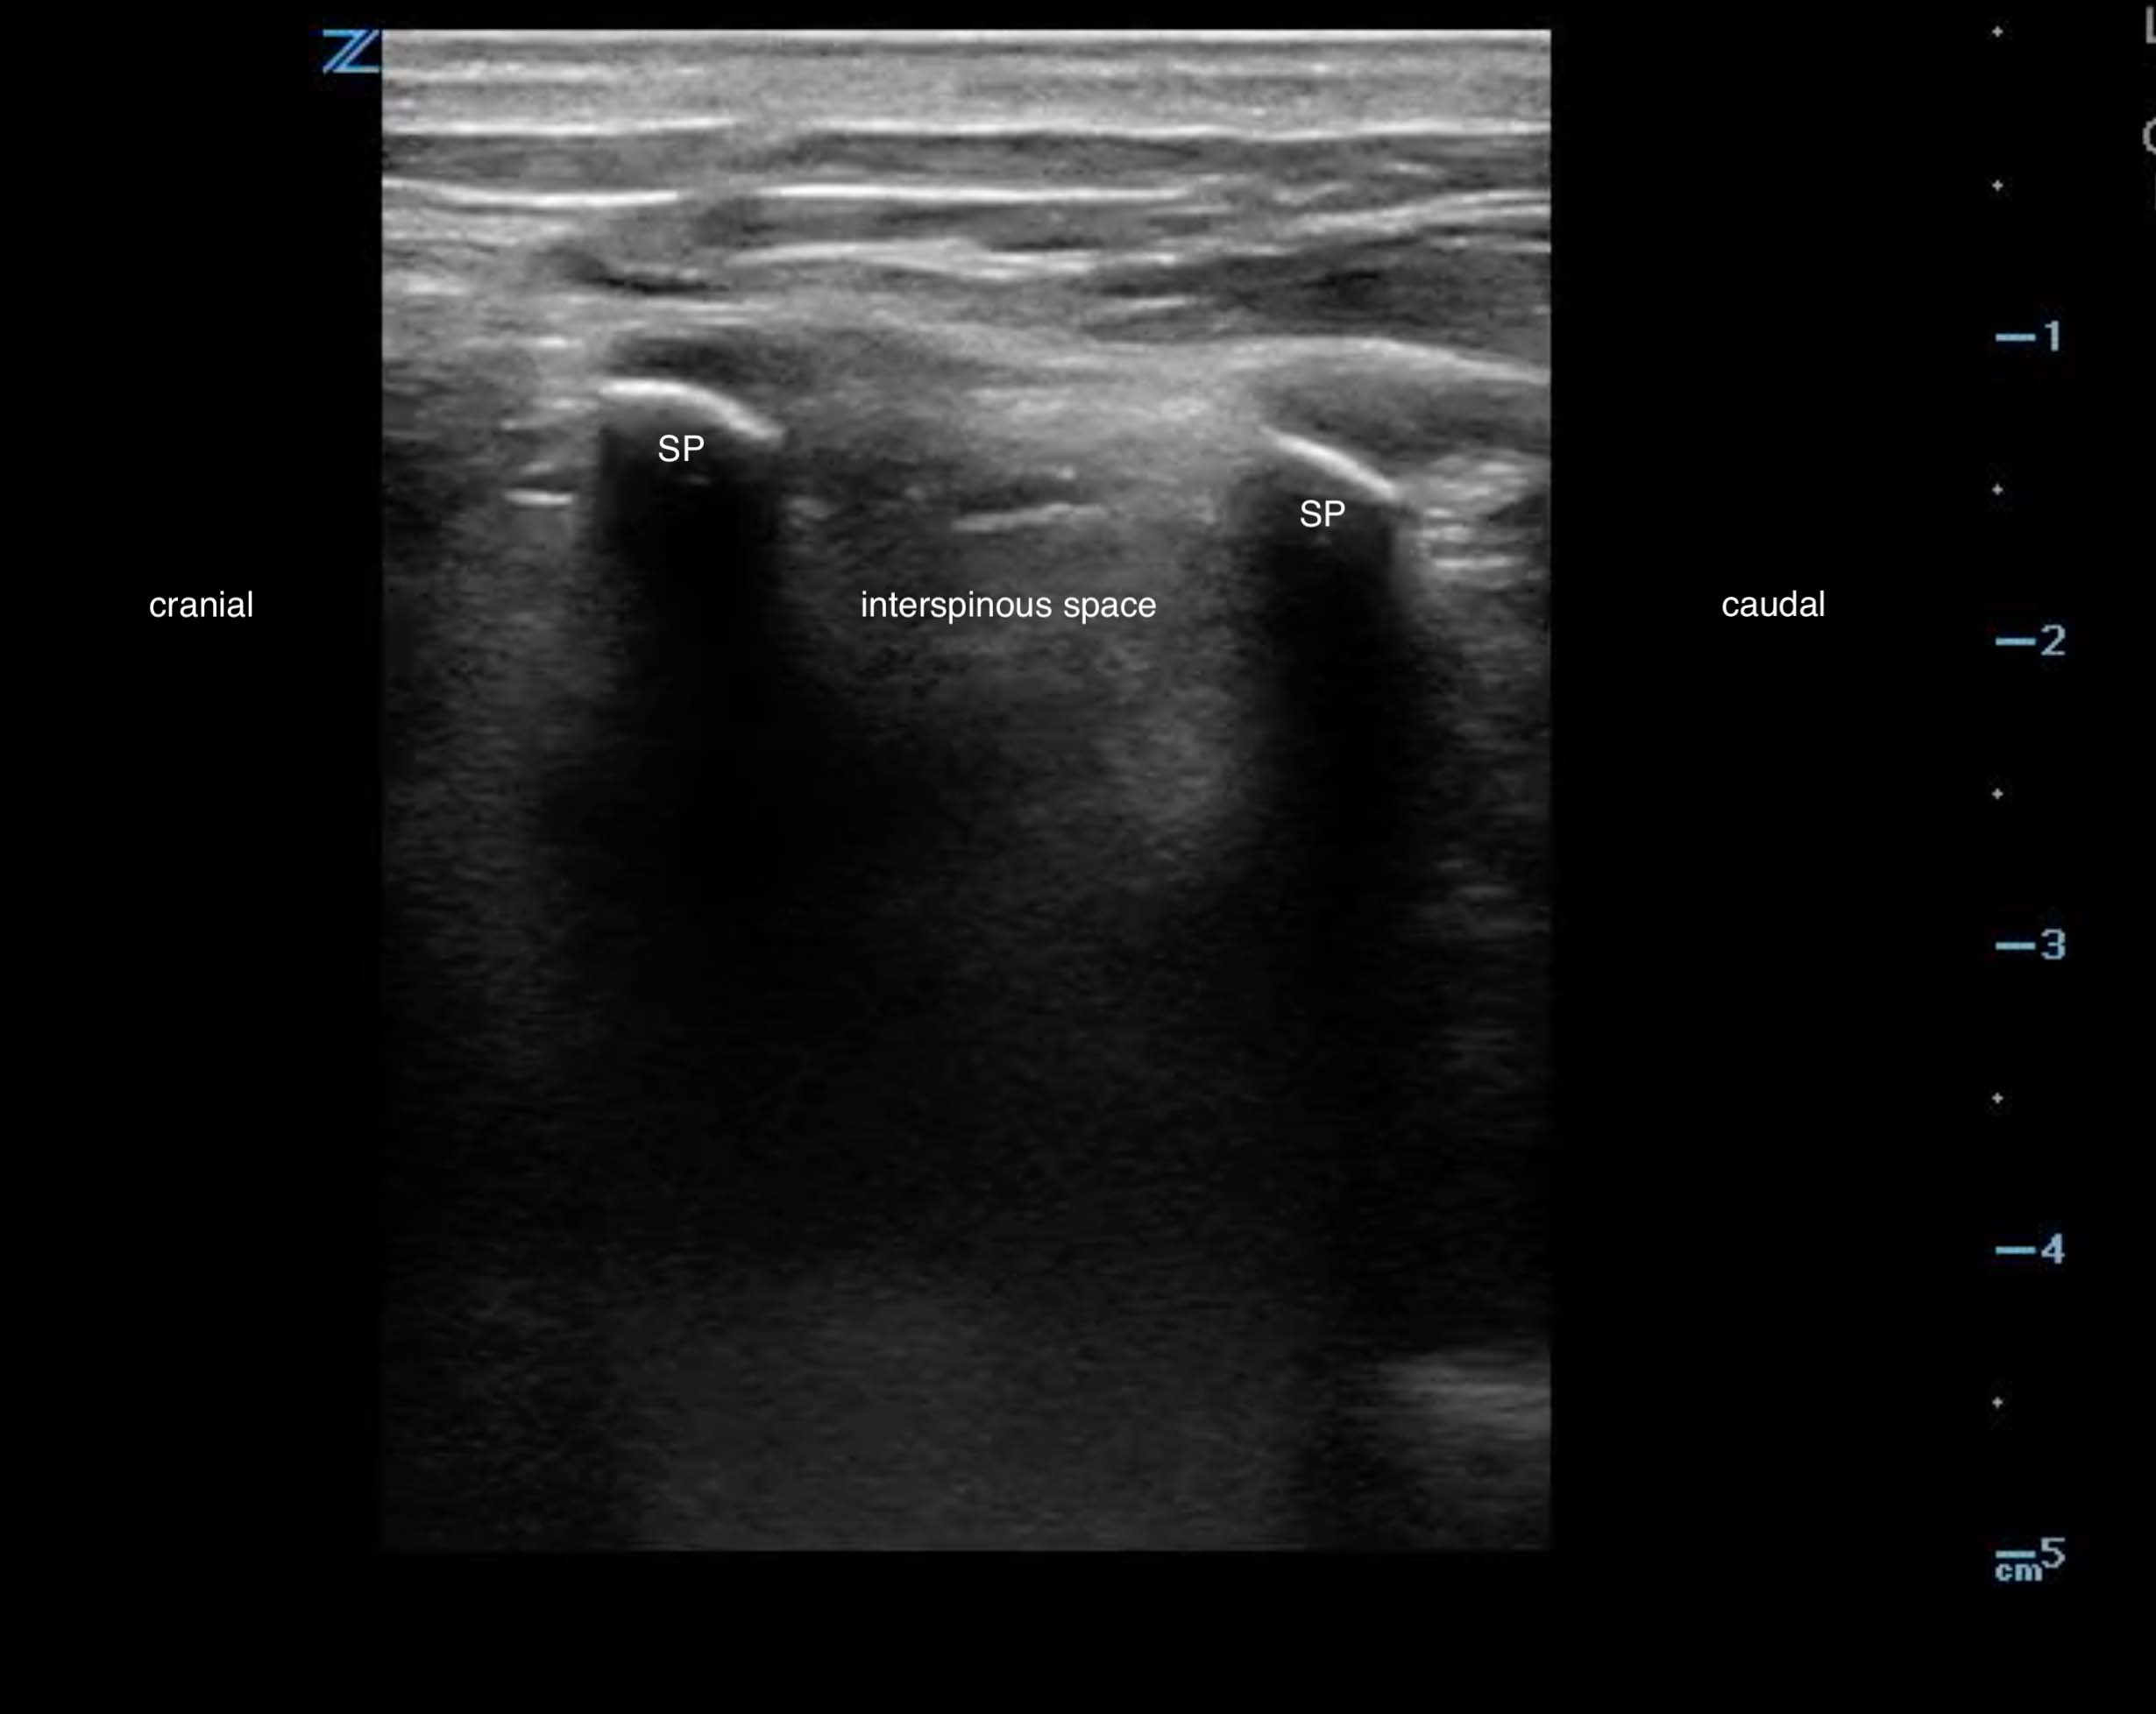

- The most pertinent structures for ultrasound identification include the L3, L4, and L5 spinous processes and interspinous space.1,3 (Fig. 1)

- Figure 1. Sagittal view spinous processes and interspinous space (adult)

- Spinous processes appear as hyperechoic crescents with acoustic shadowing